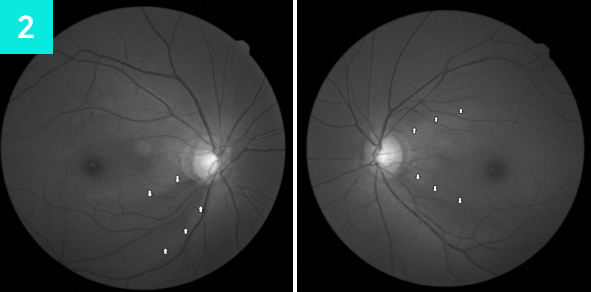

녹내장이 진행될수록 시신경 유두테의 손실이 증가하여 시야가 점점 줄어듭니다.

망막(황반) 및 시신경을 촬영하여 이상유무를 확인합니다.

정밀한 단층 촬영이 가능한 안과 CT 검사를 통해 녹내장의 초기 징후를 발견할 수 있습니다.